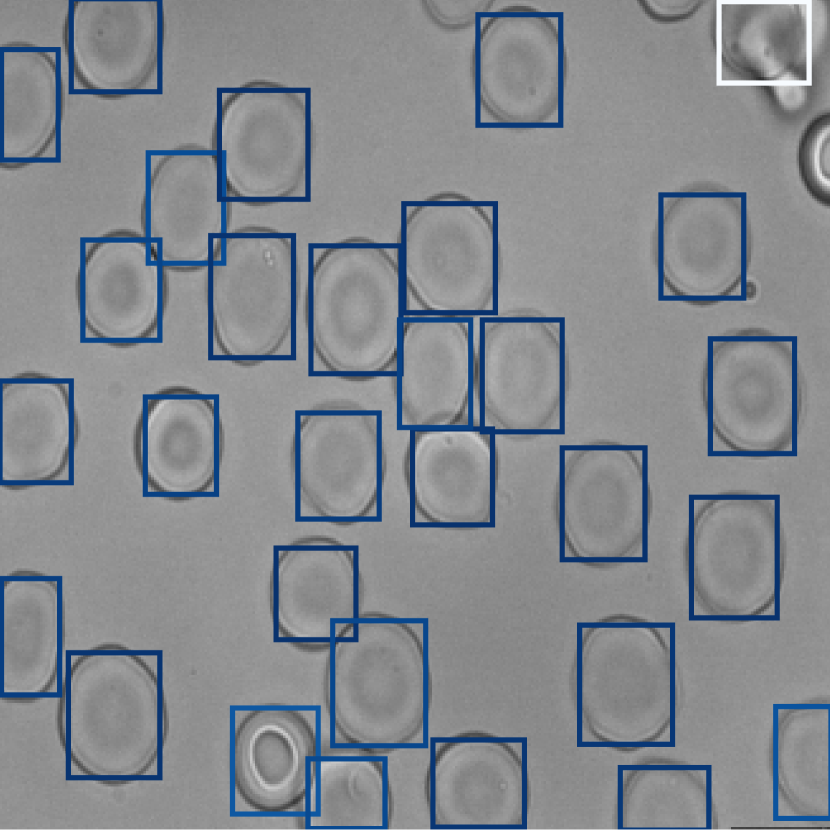

3.2 Explainability

Our method’s anomaly scoring mechanism is interpretable at the instance level. In Fig. 3, for each class, we visualized a sample image, in which anomaly and attention scores are depicted by the color of the cell’s bounding box. The anomaly mechanism can distinguish class-related cells better than the attention mechanism, which is particularly striking for the SCD case, where irregular elliptoid cells are missed by the attention mechanism (Fig. 3). In Fig. 4 we show the distribution of scores assigned to cells in the test data. The frequency of both anomaly and attention scores are focused around zero, which is compatible with a majority of healthy cells (see also Fig. 4). On the other hand, for HHA, a small distribution of high scores notifies the anomalous cells. These cells show HHA properties.

Figure 3: Interpretation of bag classification at the instance level based on anomaly (top) and attention (bottom) scores. Compared with attention mechanism, disorder-relevant cells are more accurately scored by the anomaly mechanism.